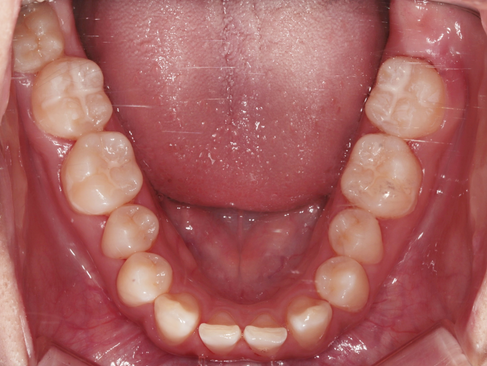

초진 시 씹는 면 구내사진 입니다.

X-ray상으로는 치아 사이의 인접면에 충치가 의심되는 부위들이 있었습니다.

치료 전후 구내사진 입니다.

치료 후 완벽하게 수복하여 치아 내부를 보호하고 있는 모습을 볼 수 있습니다.